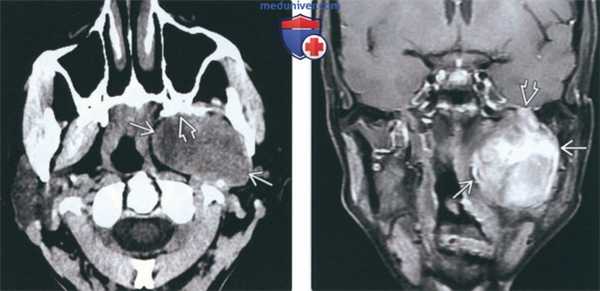

(Слева) На аксиальной КТ без КУ у пациента со шванномой ЧМН V3 визуализируется хорошо отграниченная неоднородная солидная опухоль в жевательном пространстве слева приводящая к ремоделированию крыловидных пластинок, что свидетельствует о медленном росте.

(Справа) На корональной МРТ (Т1 ВИ С+ FS) у этого же пациента визуализируется шваннома жевательного пространства неравномерно накапливающая контраст, с минимально выраженным распространением в полость черепа через расширенное овальное отверстие.